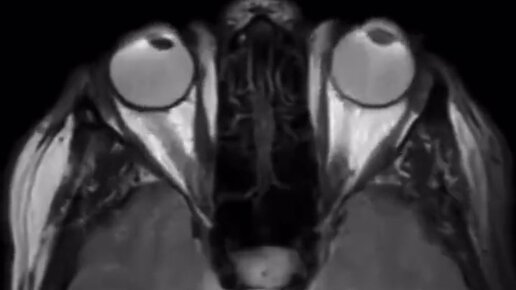

Глаза — зеркало души? А может лучше… ЧАСТЬ МОЗГА, ВЫНЕСЕННАЯ НА ПЕРИФЕРИЮ?